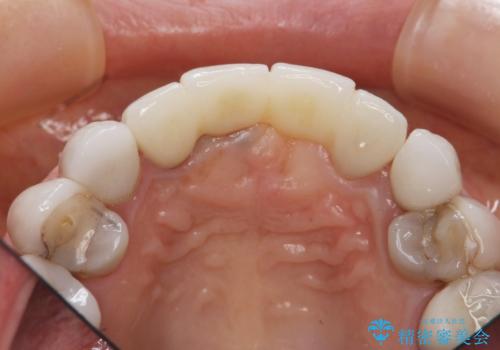

[ セラミック治療 ] 歯ぐきの際の黒ずみを改善したい

- 歯ぐきとセラミックの間の黒ずみが目立つので、きれいに治してほしい。と希望され来院されました。

歯ぐきの位置が変化しクラウン下の歯が見えるようになってしまったことで、審美障害が生じている状態です。

クラウンマージンの再設定を行うことで、黒ずんだ部分を再度覆い、審美障害を改善します。

- 52.8万円(ジルコニアクラウン×4・仮歯×4)費用は治療当時の料金となります